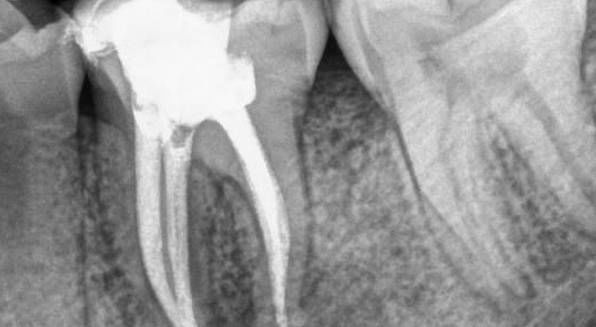

1、根管治疗是以药物以及器械的操作来将根管内的残渣以及细菌尽可能地清除消毒干净。然而,这样的消毒过程如果要认真的进行,却必须去除掉不少被细菌感染的牙齿,以及不得不修整的牙体组织。所以大部分的牙齿一旦进行根管治疗,则可能不太足够支持咀嚼的力量而可能断裂,单纯用材料已经没法恢复功能,即使能恢复长远效果也不好。

2、经过根管治疗后的牙齿失去了来自牙髓的营养供应,就像失去树根的树木一样,慢慢枯萎变的很脆弱,造成牙齿的脆性增加,易劈裂。

3、因为需要进行根管治疗的牙齿一般已是龋病(虫牙)、缺损很大,这时虽然根管治疗完成,但是其所剩的牙体组织是很脆弱的,非常容易折断、裂开,失去正常的功能,单纯用材料已经没法恢复功能。

1、仅仅个别牙尖或少部分牙劈裂,剩余的大部分牙体稳固,没有咬合疼痛,拍牙片无根尖病变!

需要的治疗:可将劈裂的活动的部分拔掉,再做冠修复。

2、若劈裂刚刚发生,部位在牙体中央,两部分都不松动,不疼痛,牙龈无红肿,无咬合痛,拍片根尖部位无病变。

需要的治疗:可将牙齿劈裂的两部分结扎牢固后,再做冠修复。